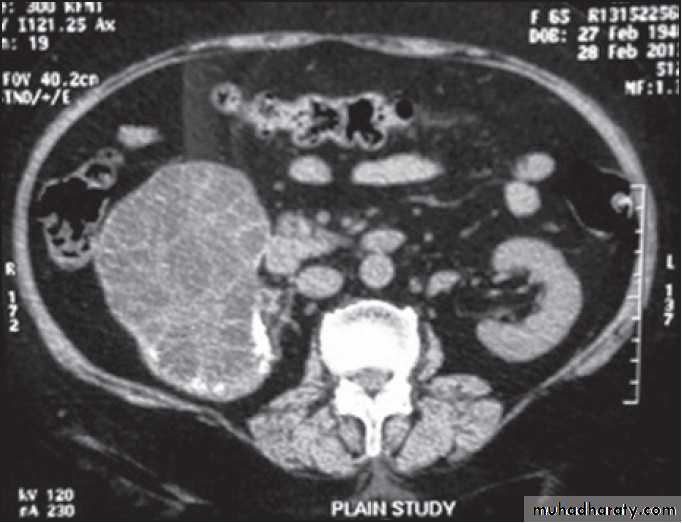

SerologyPlain X-ray

U/S

CT